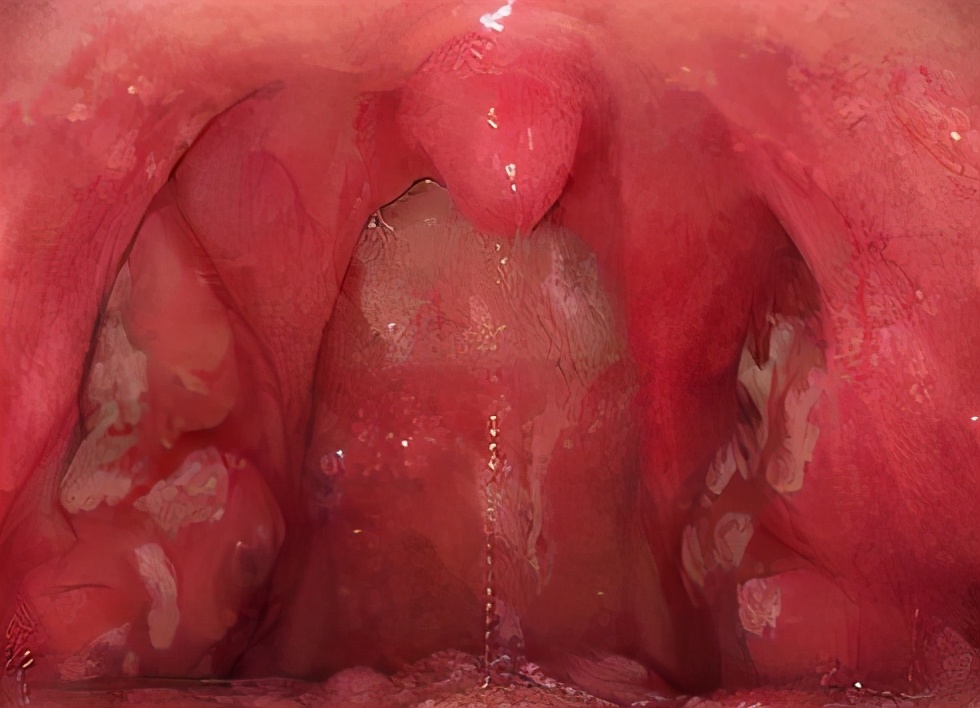

1.咽峡部位

猩红热的宝宝一般会有咽痛、吞咽痛的表现。

这时让娃张开嘴巴,重点查看娃的扁桃体是否有局部充血、或脓性渗出液现象。

咽部后壁及扁桃体明显红肿充血

白点为脓性渗出液

图片来源:网络